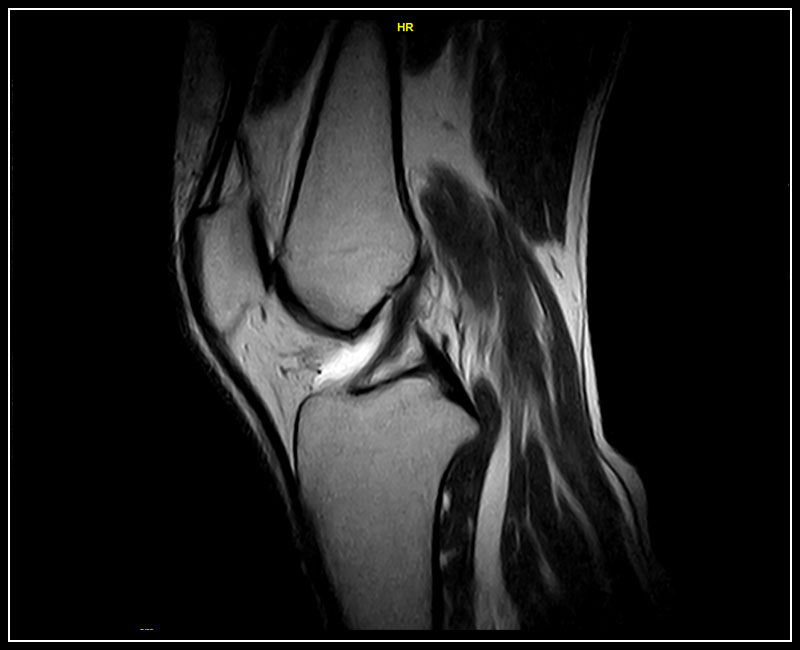

Klinické snímky

• Vysoká kvalita snímků

• Kompletní sada sekvencí včetně turbo sekvencí, získávání v ustáleném stavu a X-Bone. G-scan Brio přichází s velkou sadou specializovaných sekvencí vhodných pro všechny požadavky na zobrazování MSK